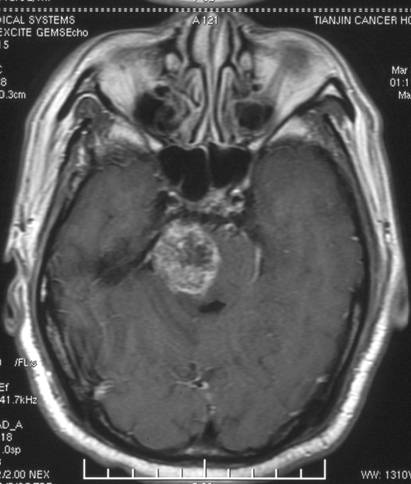

脑干胶质瘤:

治疗前

治疗后